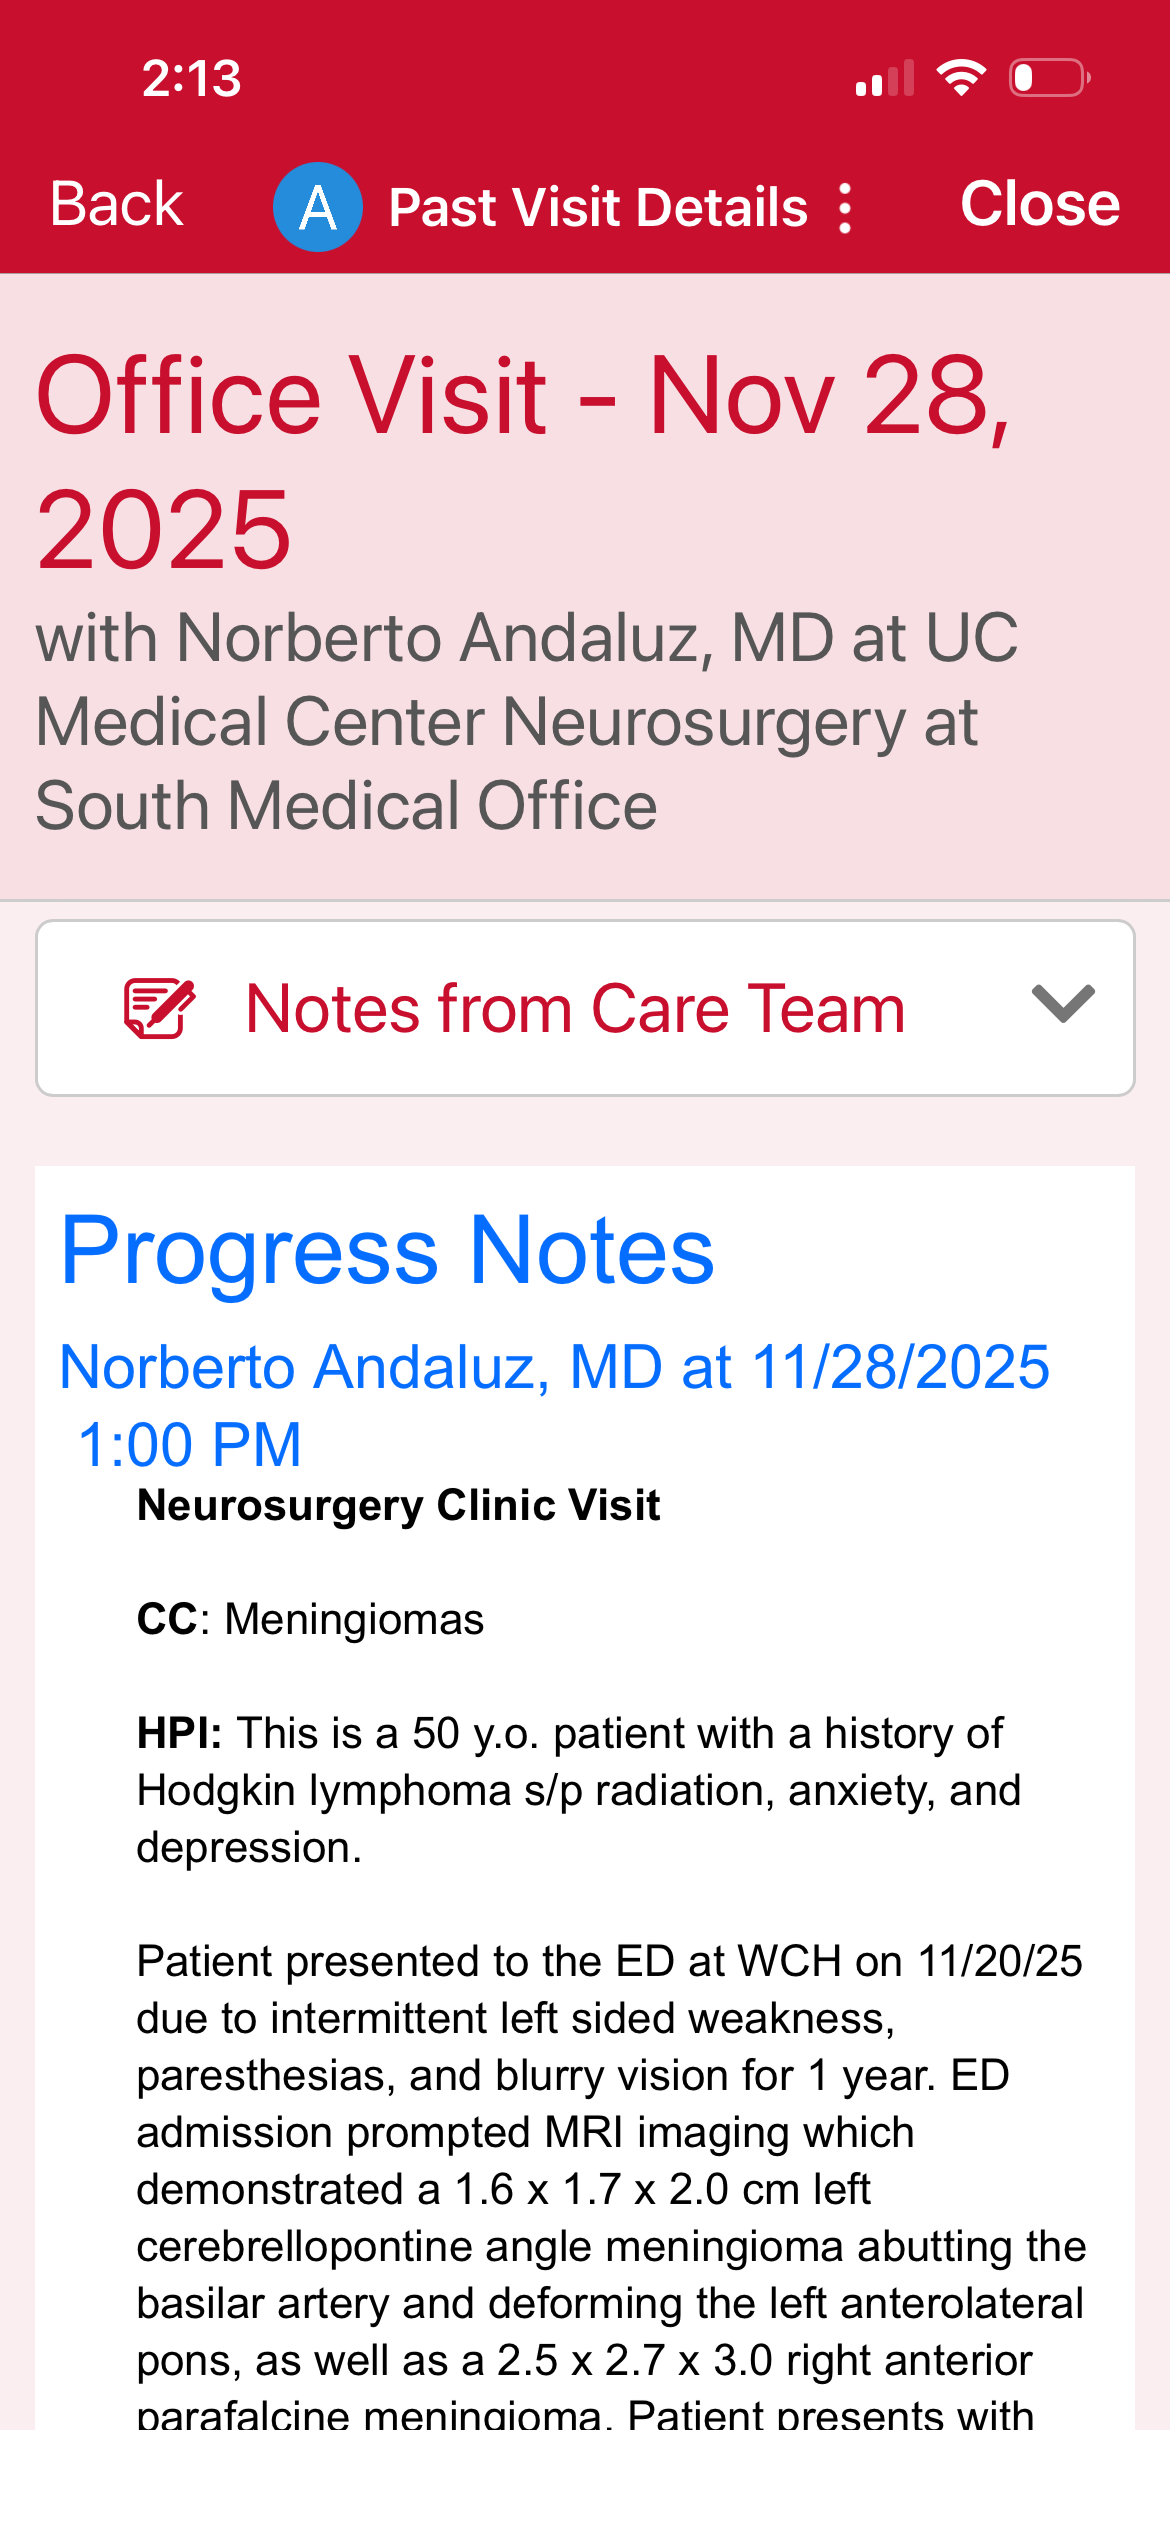

My name is Kory Burge and I'm raising funds for my mom, Angela Montgomery. She is a pediatric cancer survivor, prior pediatric oncology nurse and amazing mom and Mimi. When she was being treated for Stage III B Hodgkin’s Lymphoma in 1991 at the age of 16, they told my grandparents that the long-term concern is developing another cancer due to the harsh chemotherapy and radiation protocol, as well as heart and lung disease. As a parent, what choice do you have? Thirty-five years later, on November 18, 2025 after complaining for over three years to her doctors that something was desperately wrong and being denied an MRI, she convinced the ER doctor to do a CT on her head. They found two large brain tumors, one of which is pressing on and displacing her brain stem. She also has some on her spine, but they’re not sure how many yet. MRI of her entire spine is coming March 6th. This has kept her from working and she has used her retirement down to the penny, and now cannot work, nor support herself through this. Please donate if you can and share this with everyone you know.

The donations will be used for transportation to the multiple appointments and surgeries she needs, rent, utilities and any co-pays she’s responsible for. I take her to all appointments because she’s struggling to drive. Her left leg has given out multiple times and she has always stubbornly insisted on driving a stick shift. She’s unable to hold the clutch in now :( Her most recent fall resulted in a huge bruise/hematoma on her right arm.

The plan is to have the first surgery on March 10th to remove the brain tumor currently displacing her brainstem before it starts causing seizures. It will be 10-12 hours long, then 3 days in ICU and 3 days on the unit. The next will be to remove the one in her frontal lobe.

It started out with her memory slipping. She would forget simple conversations we’d had hours before. She kept bumping into things and the headaches are so horrid. It’s hard to watch the fiercest woman you’ve ever known reduced to tears because she can’t find words during a conversation. She said it feels like she’s going crazy.